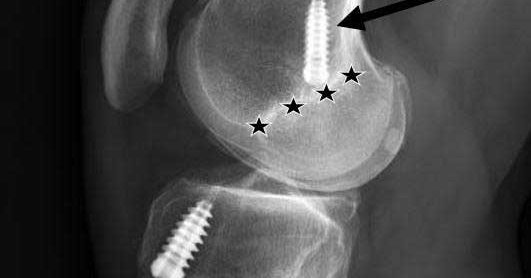

After proximal tibiofibular joint reconstruction: • Non-weight bearing or toe-touch 6 wks • No deep squats/twisting 4 mos • Stationary bike at 6 wks • Return to full activity 4–6 mos Strength & stability first! https://t.co/8IfS5UMq4h #OrthoTwitter

Proximal tibiofibular joint instability is rather rare, but can be debilitating in patients who have symptoms.